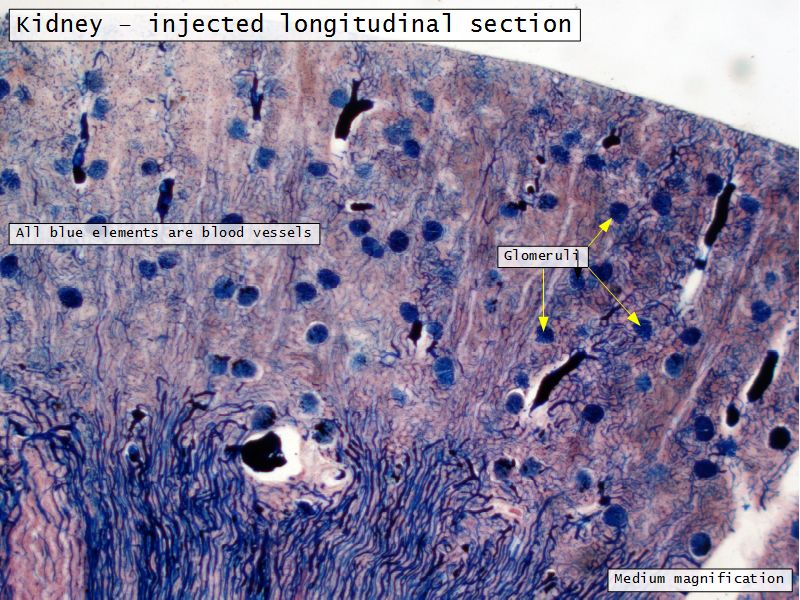

Kidney

- Capsule

- Cortex

- Medulla

Appearance

- Cortex

- Renal corpuscles

- Convoluted tubules

- Medulla

- Loops of Henle

- Collecting tubules

Kidney lobule

- Group of neprons

- Open into branches

- Same collecting duct

- Not clearly demarcated

- Interlobular arteries/veins

Renal corpuscle

- Tuft of capillaries

- grow into

- Blind end of nephron

- Several layers of epithelium

- Two sides

- Vascular pole

- Tubular pole